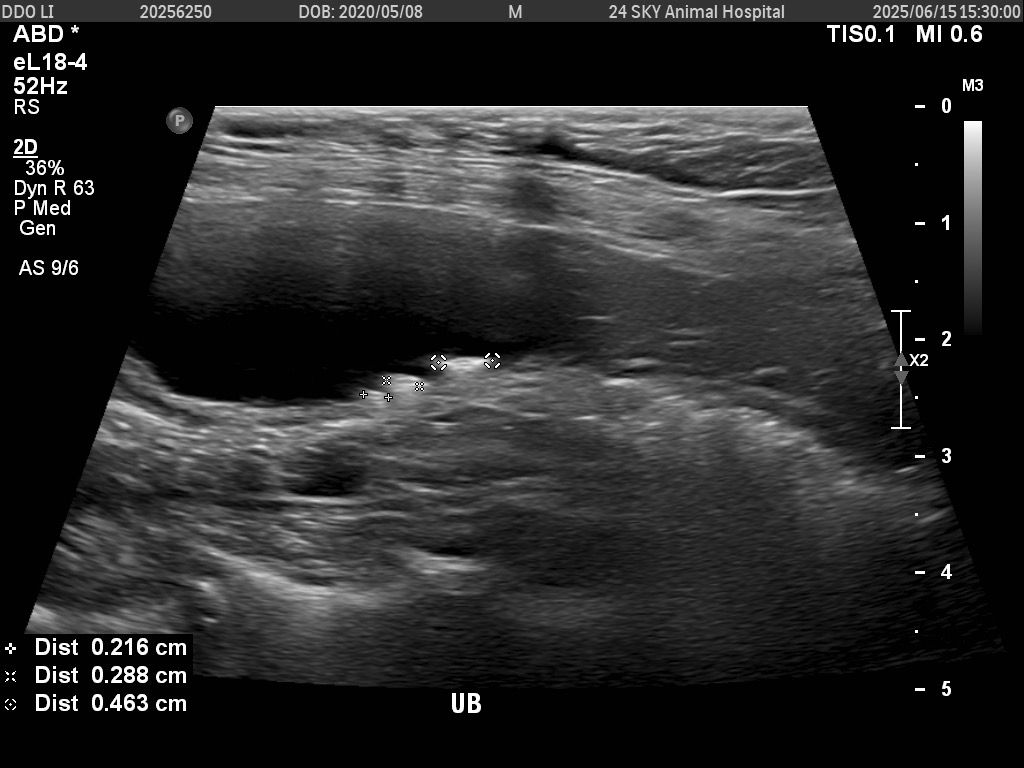

그런데 오늘 6월 15일 다시 내원했을 때

방광 쪽에는 0.216cm, 0.288cm, 0.463cm 크기의 결석 3개가 확인되었다고 들었습니다.